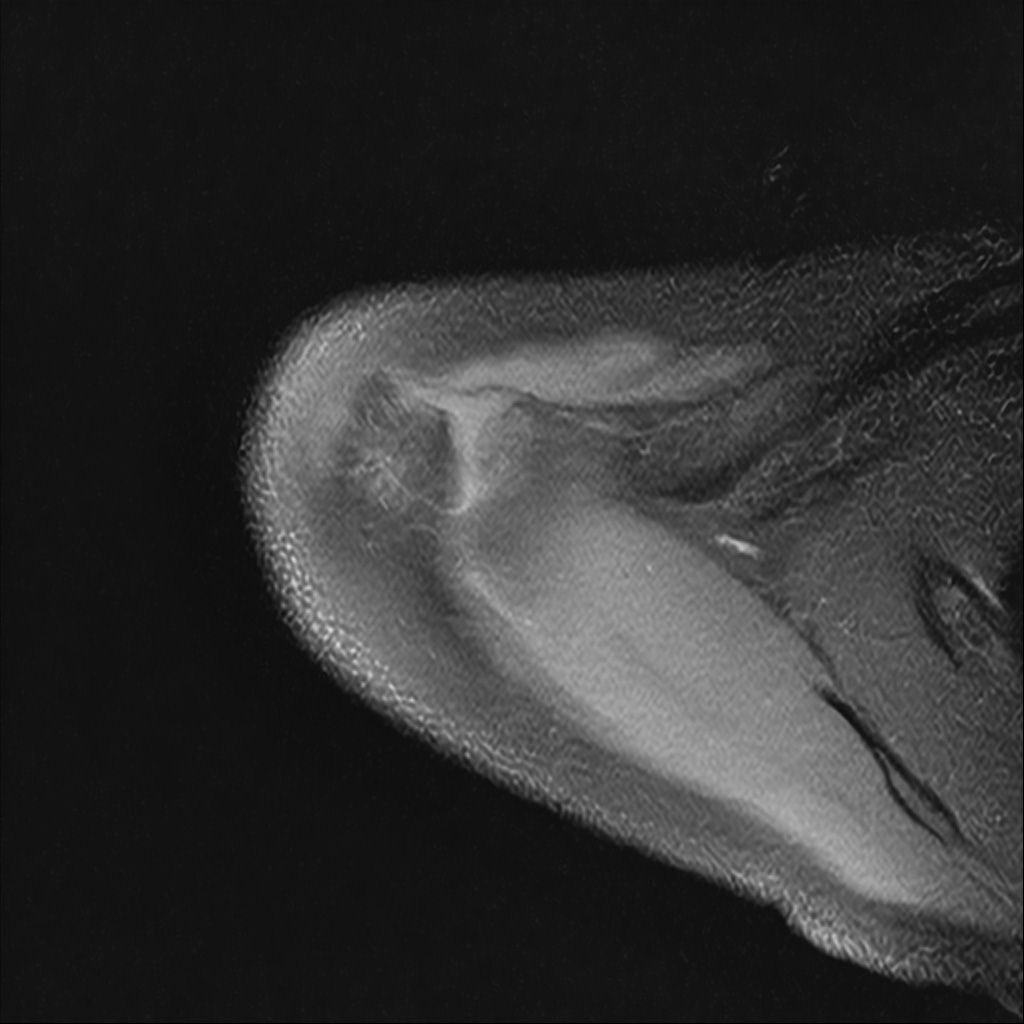

Mri 단면 영상으로 보아 어깨 관절 부위에서 이상 신호가 관찰되고 이는 관절 와순 파열의 가능성을 시사할 수 있습니다.

하지만 이영상만으로 정확한 진단은 불가능하고 정밀한 판단을 위해선 전체 시퀀스와 영상의학과 전문의의 공식판독이 필요합니다 특히 와순 파열은 위치와 동반 병변에 따라 해석이 달라집니다!